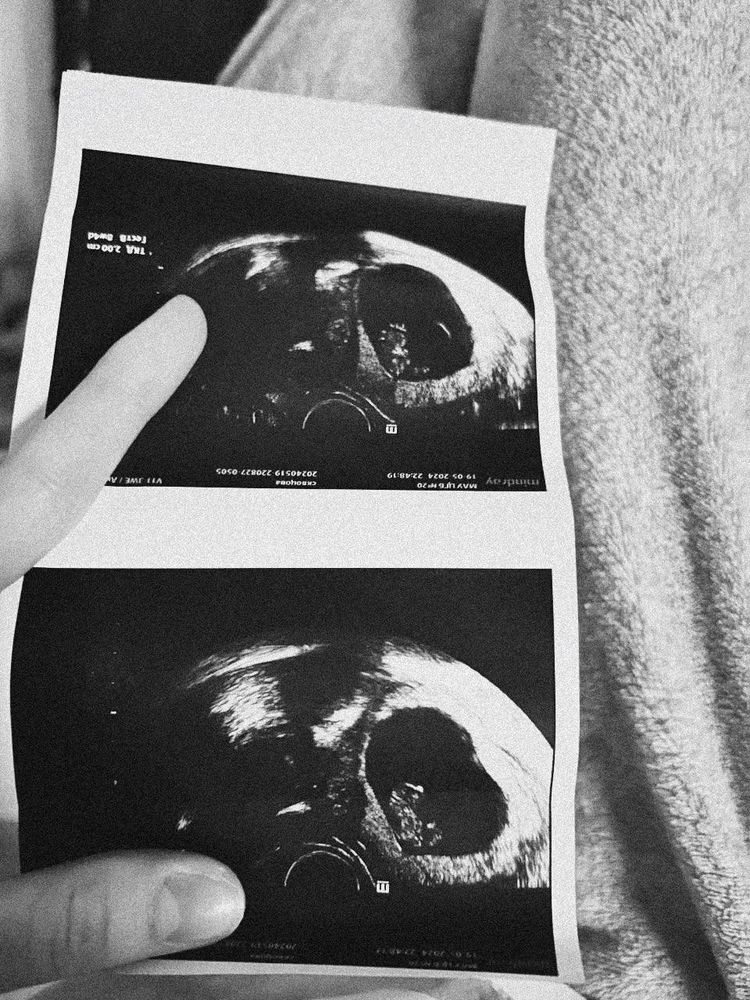

Всем здравствуйте! Был пост о том что на 5 неделе нашли гематому, сегодня срок (6 недель и 4 дня) врач никакой гематомы не увидела (наверное сбежала от меня 😄) ПЯ 21 мм, эмбрион КТР 8мм, услышали сердечко 122 уд/мин. У кого такой же срок, расскажите что у вас было?) Интересно было бы почитать

Была на подтверждении беременности на 7 неделе ,но сердце не слушали.

На 8 неделе попала в больницу ,там первый раз услышала сердечко)

Такой дракончик был)

Такой дракончик был)